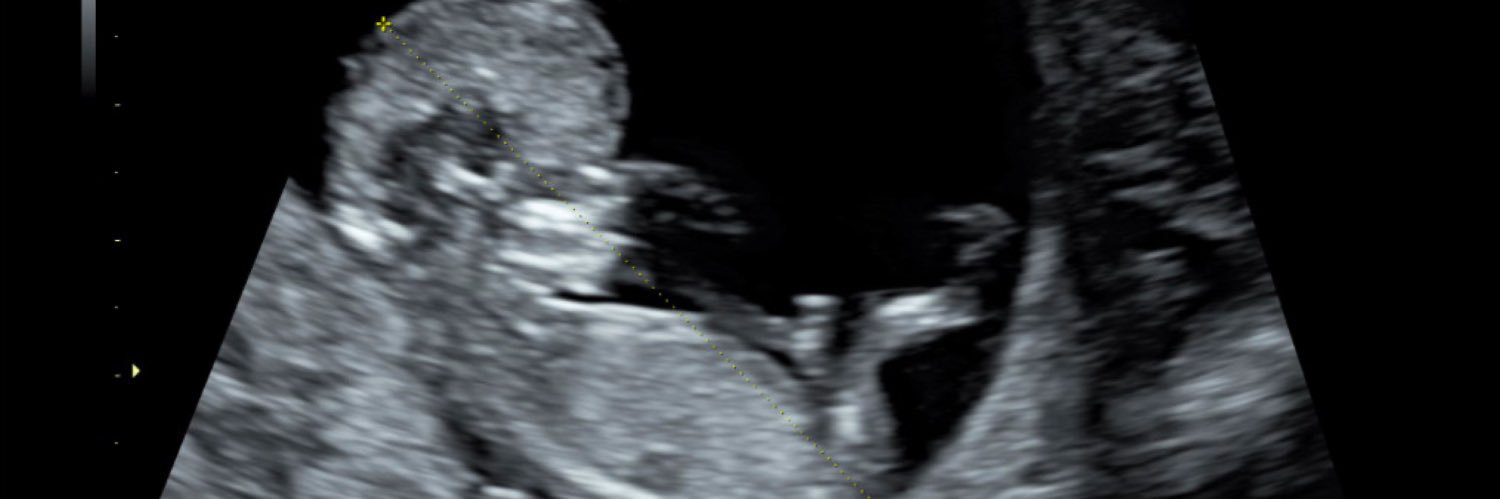

Advancing discovery to protect pregnant people and their babies during COVID-19

We are honored to be the @study_aspire Clinic of the Week! Researchers at @UCSF are working to understand the implications of #COVID19 exposure during #pregnancy. We are thrilled to partner with centers across the US for this initiative: aspire.ucsf.edu. #COVID19de #netde